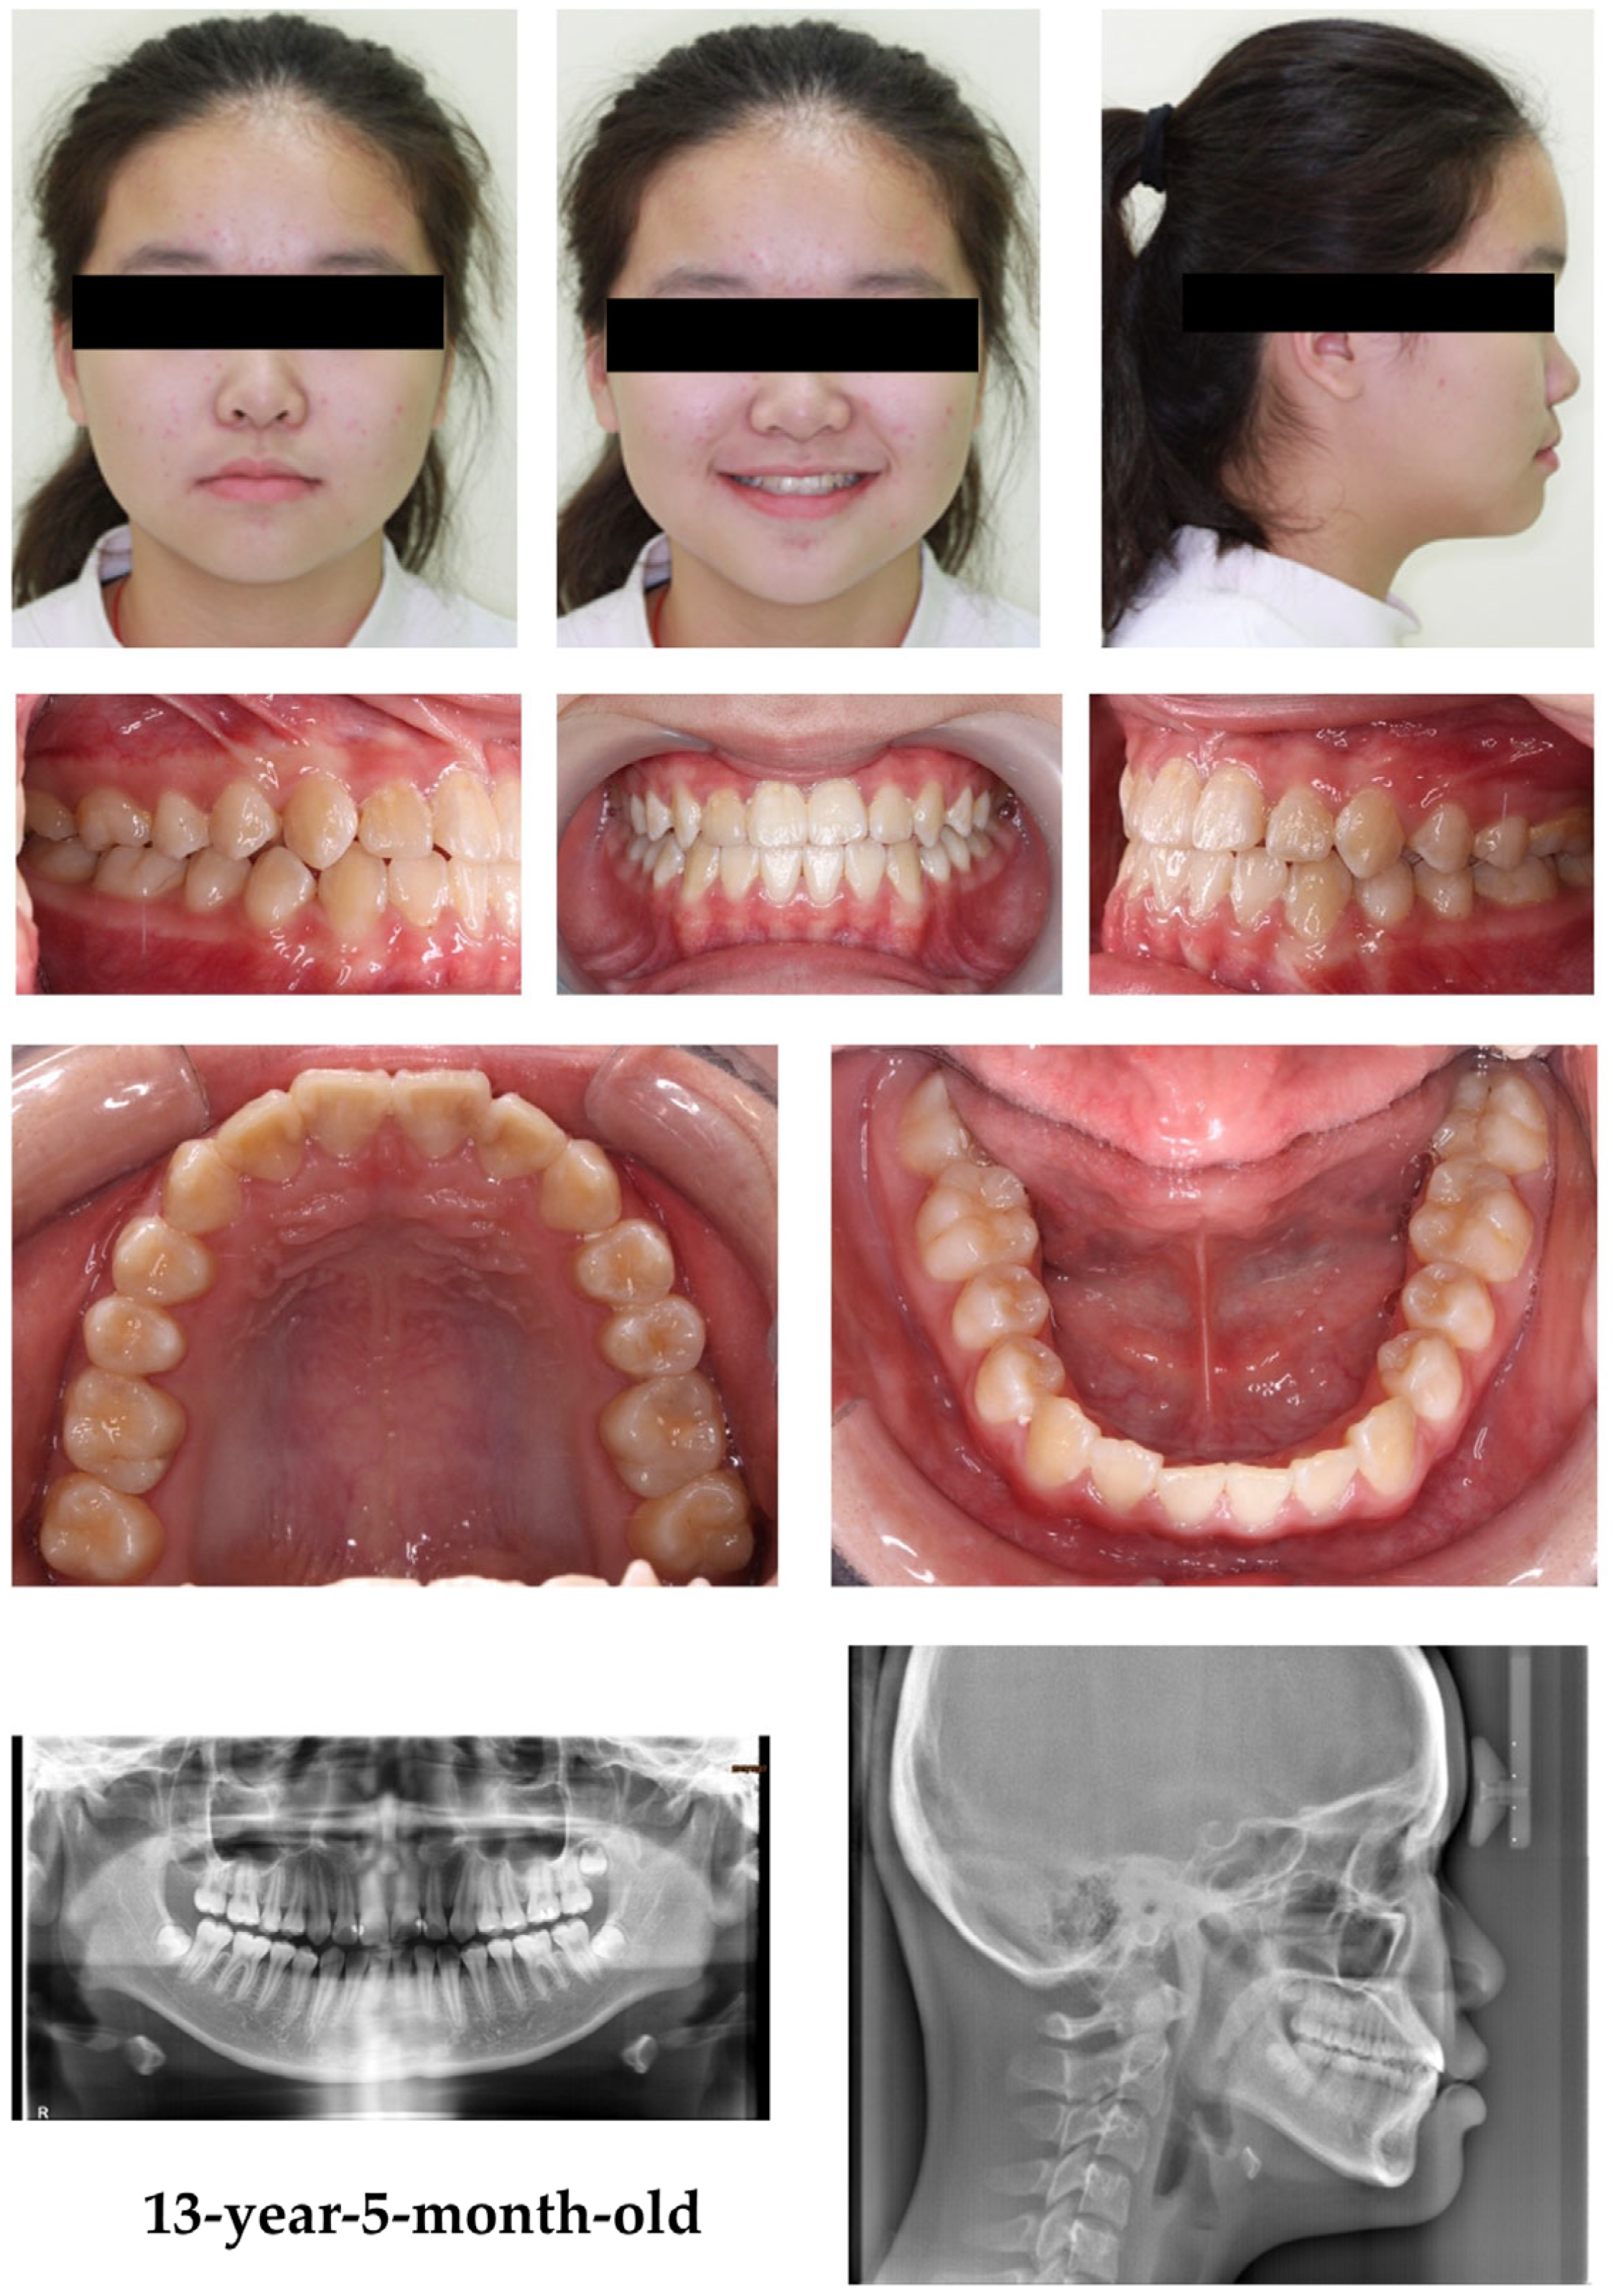

2.1. Patient Information and Clinical Findings

2.2. Treatment